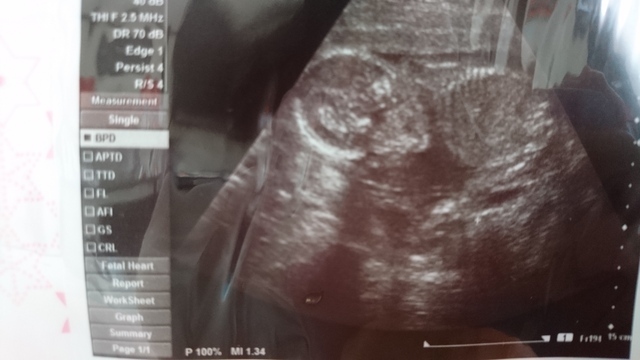

20週2日(20w2d・男の子)|はぎくみ さん(25歳)

エコー写真撮影時のエピソード:

この日初めて背骨が見えてすごく感動したのを覚えています。それまではずっと丸が二つくっついたようなドラえもんみたいな形のエコー写真だったので、もうこんなにおおきくなったんだなぁって。人間らしくなってきたんだなぁと。

それなのにお家に帰ってから旦那と母に見せたら怖い!ガイコツみたい!と言われ怒りました(笑)